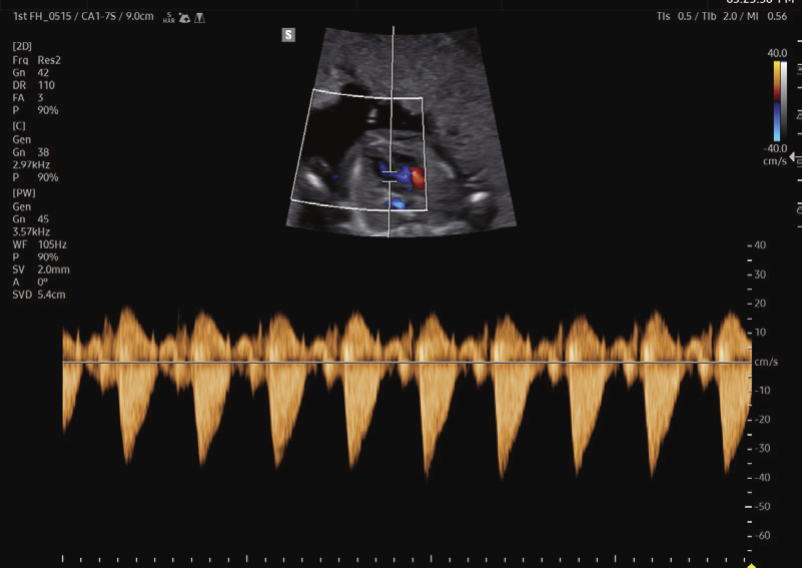

Imagens Clínicas

Recursos 2D/3D/Color avançados para saúde da mulher